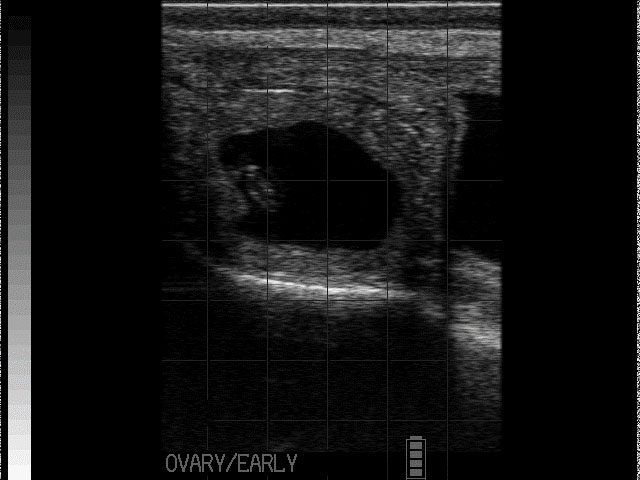

Follicular cysts are typically large, thin-walled (<2-3mm), round, black structures that are often single but can be multiple (see Photo 1)2,4. Traditionally, follicular cysts were defined by being greater than 25mm in diameter and persisting for longer than 10 days but recent work would indicate that follicular cysts can be present and only measure 16-17mm in diameter2. Cows with follicular cysts will have low peripheral progesterone concentrations and typically present anoestrous but can be nymphomaniacal if the cyst is actively secreting oestradiol4. However, that stated, follicular cysts are still dynamic structures which can luteinise (forming a luteal cyst), or become inactive and regress. In situations where they have begun to regress, the cystic structures can be noted in cows who have started to cycle again (i.e., some of these cows will have CLs) or even those cows who have become pregnant.